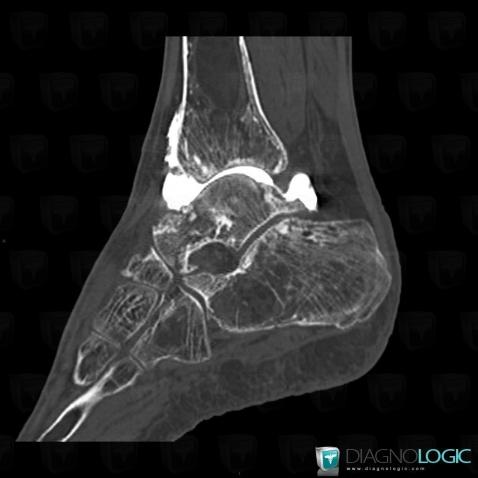

Avascular necrosis, Tibia - Distal part, CT

Here is the specific information in the key image above:

- Diagnosis Avascular necrosis, Location(s) Tibia - Distal part, with gamuts Ill-defined osteolysis

- Diagnosis Bone infarct, Location(s) Tibia - Mid part, with gamuts Mulltiple osteolysis, Diaphyseal osteolysis